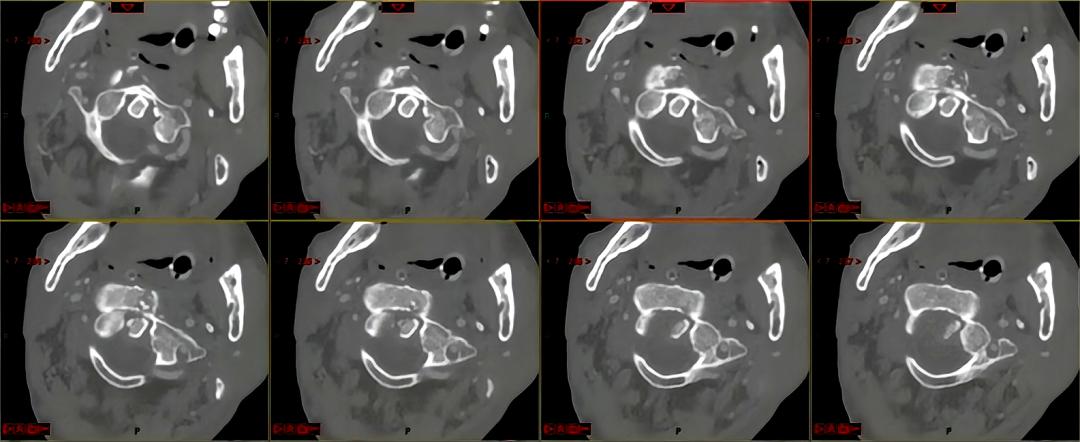

老黄摔伤后当即出现四肢瘫痪、呼吸困难,路人拨打120后老黄被紧急送到保亭县人民医院时,医生们倒吸一口冷气:CT及核磁检查后发现,老黄虽然人还清醒,但是伤情异常严重,上颈椎粉碎性骨折、寰枢椎旋转侧倾脱位、高段颈髓受压致神经损伤,枕颈交界区的骨折造成的不稳定已危及延髓生命中枢,老黄到达医院后数次出现呼吸骤停,命悬一线!

上颈椎骨折后:断裂破碎和脱位的颈椎与关节、盘绕的椎动脉

颈椎骨折后神经损伤:受压严重、扭曲的颈髓